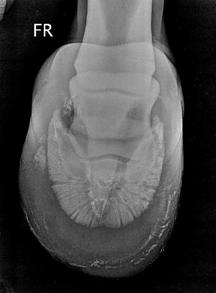

Lūžio diagnozei patvirtinti yra atliekamas radiologinis galūnės tyrimas. Daugumą lūžių galima nustatyti atlikus dorsoproksimalinę-palmarodistalinę įstrižą rentgenogramą.

Jei kyla abejonių, atliekama rentgenografija dorsopalmarine ir palmaroproksimaline-palmarodistaline įstriža projekcija (14 pav.). Palmaroproksimalinė-palmarodistalinė įstriža projekcija naudinga įtariant daugybinius ar dislokuotus lūžius (Ross M.W., Dyson S.J., 2003).

Daugybinis lūžis Paprastasis lūžis

Netaisyklingas

lūžis Varlės

kaulų sparno lūžis

14 pav. Dažniausiai pasitaikantys varlės kaulo lūžiai (Turner T.A, 1999).